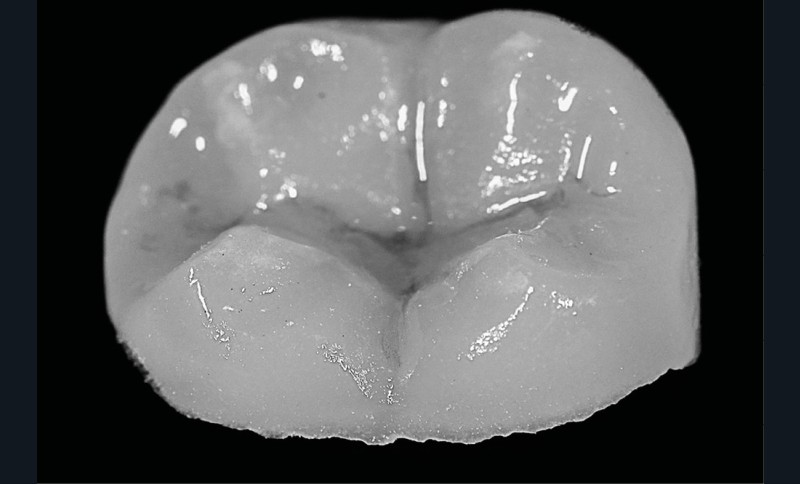

La compréhension de ces instruments, des biomatériaux et des différentes techniques est essentielle, et doit nous guider dans nos prises de décision en fonction des situations cliniques. Dans le cas clinique présent, suivi sur 24 mois, le patient se présente avec des douleurs à la mastication sur la dent 36. Tous les signes cliniques (test au froid négatif, test à la percussion positif, sondage parodontal positif en vestibulo-distal avec présence de fistule) et les examens radiologiques (LIPOE sur la racine distale, lésion inter-radiculaire) convergent vers un diagnostic de nécrose pulpaire due à une fracture longitudinale non complète (type 3 : Classification AAD) [1] (fig. 1).

La procédure clinique est construite en deux séances. Lors de la première séance, d’une durée de 3 h, nous effectuons l’endodontie, la base intermédiaire, la préparation de l’overlay, et l’empreinte optique. La cavité d’accès réalisée est aussi petite que possible, mais aussi large que nécessaire afin de favoriser un maximum de préservation tissulaire tout en permettant un accès raisonnable aux canaux (fig. 2).